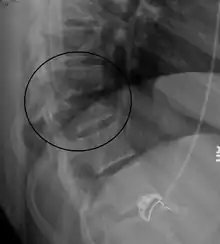

Chance fracture

A Chance fracture is a type of vertebral fracture that results from excessive flexion of the spine.[8] Symptoms may include abdominal bruising (seat belt sign), or less commonly paralysis of the legs.[4][9] In around half of cases there is an associated abdominal injury such as a splenic rupture, small bowel injury, pancreatic injury, or mesenteric tear.[3][5] Injury to the bowel may not be apparent in the first day.[10]

| A Chance fracture of T10 and fracture of T9 due to a seatbelt during an MVC. | |

The cause is classically a head-on motor vehicle collision in which the affected person is wearing only a lap belt.[2] Being hit in the abdomen with an object like a tree or a fall may also result in this fracture pattern.[11][9] It often involves disruption of all three columns of the vertebral body (anterior, middle, and posterior).[7][6] The most common area affected is the lower thoracic and upper lumbar spine.[6] A CT scan is recommended as part of the diagnostic work-up to detect any potential abdominal injuries.[5] The fracture is often unstable.[1]